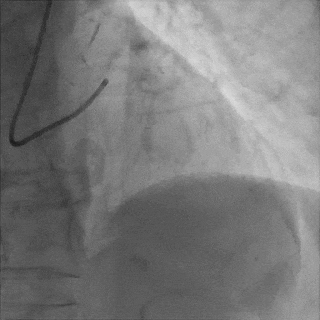

Sion导丝至LCX远端,预扩球囊扩张后,植入支架XIENCEAlpine 2.25*23mm支架一枚

术后造影支架膨胀良好,血流TIMI3级